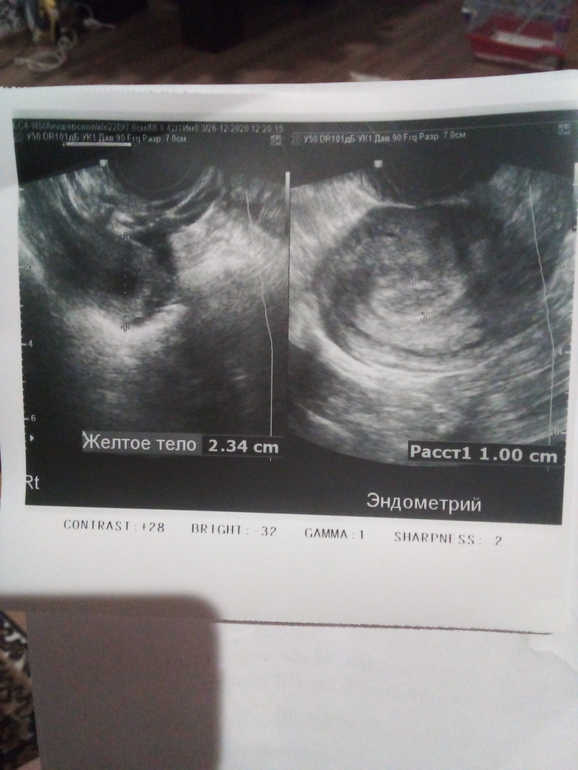

Добрый вечер, была сегодня на узи и не нашли плодное яйцо...может рано пошла? Овуляция была примерно 3-8 декабря, первый приветик( очень слабый ) увидела 14 декабря. Что скажете? И очень смущает точечка в углу где фото эндометрия, да и сам эндометрий😢 тест сегодняшний в обед после узи, хгч сдала будет готов в понедельник вечером только

Аппарат уже да, старенький, как клиника открылась в 2007 году так и есть, да и врач уже в возрасте🙈желтое тело сначала сказал что это плодное яйцо и что у меня вм, но у меня то ничего не болит а при таком размере уже боли бы были...потом подумал и поставил что это все таки желтое тело😂

Так рано ещё очень! И в заключении написано, что ПЯ ПОКА не видно. У Вас Б 5 недель, и это по месячным. Малыш ещё очень маленький.

Мне кажется рано пошли.у вас недель 5 может и не видно. Но эндометрий мне кажется маловат вообще для беременности

Мне тоже кажется маленьким но почитала в инете на эту тему и там пишут что допустимо, что главное больше 8))

У Вас отличный эндометрий! Белоконь пишет, что от 7 мм нормальный эндометрий для развития беременности.